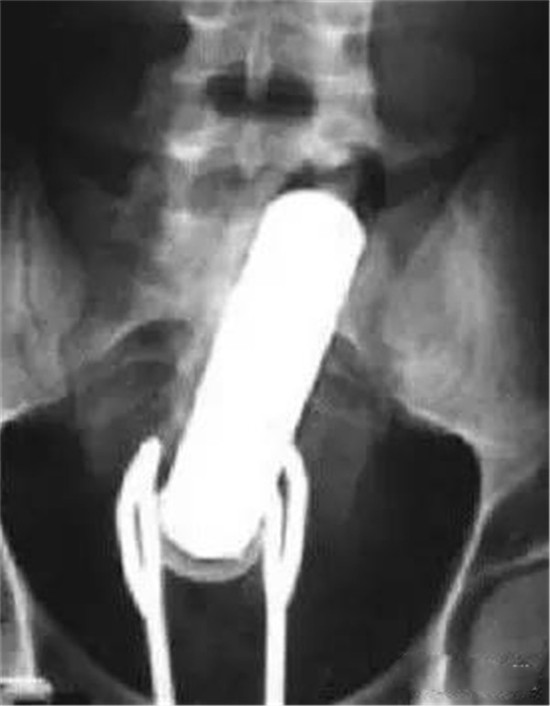

透视下从肛门里夹取直肠里的东西

一般情况下,这些肛门异物的病人,来到医院后,医生都会给他上麻醉。把病人麻醉后,在透视下从肛门里夹取直肠里的东西。

上面图片是产钳,从直肠里把直径8厘米的圆球拽出来。